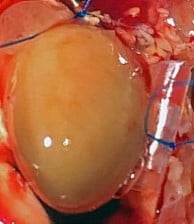

LAD Reperfusion Model: 30 Minute Ischemia with 2 Hour Reperfusion

Pictured: Cardiac Perfusion With Evans Blue Dye To Define Infarct zone.